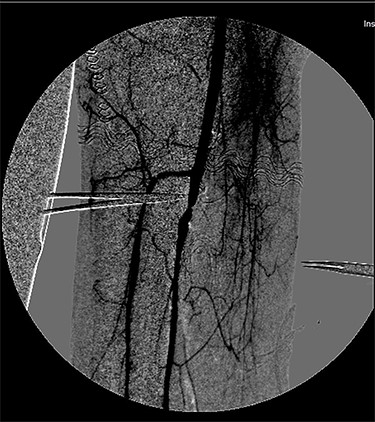

Completion angiography demonstrated the patency of the femoro-popliteal axis and of the tibial vessels (Fig. 3). Anterior and posterior fasciotomy of the leg was performed. At the end of the procedure a CW-Doppler was made showing triphasic-flow in the anterior and posterior tibial artery.

Completion angiography demonstrating patency of the popliteal artery, anterior tibial artery, posterior tibial artery and peroneal artery.